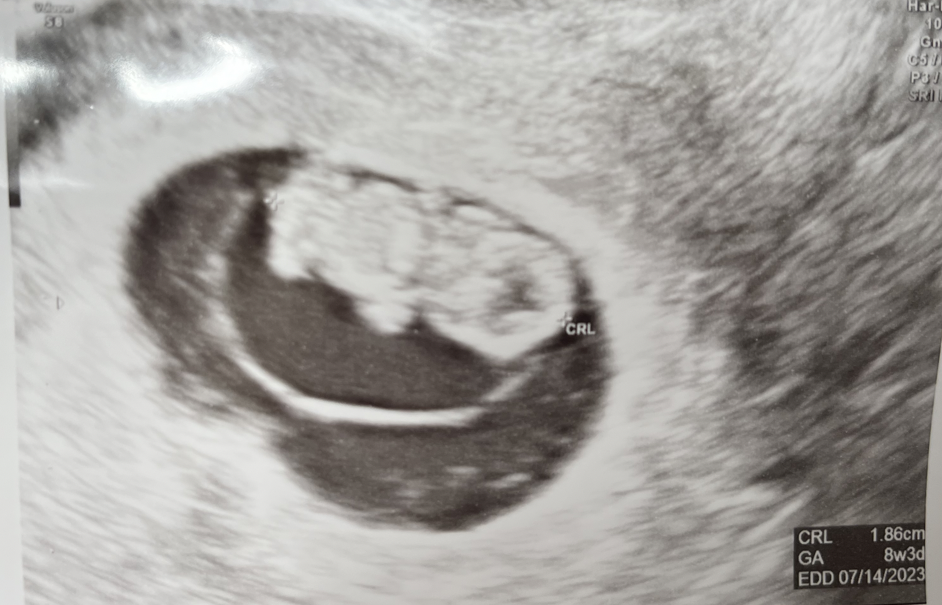

It was a wonderful winter. Apart from all the holiday activities, we celebrated our one year (California) wedding by eating our wedding cake, went to a New Pornographers concert, and saw the baby grow.